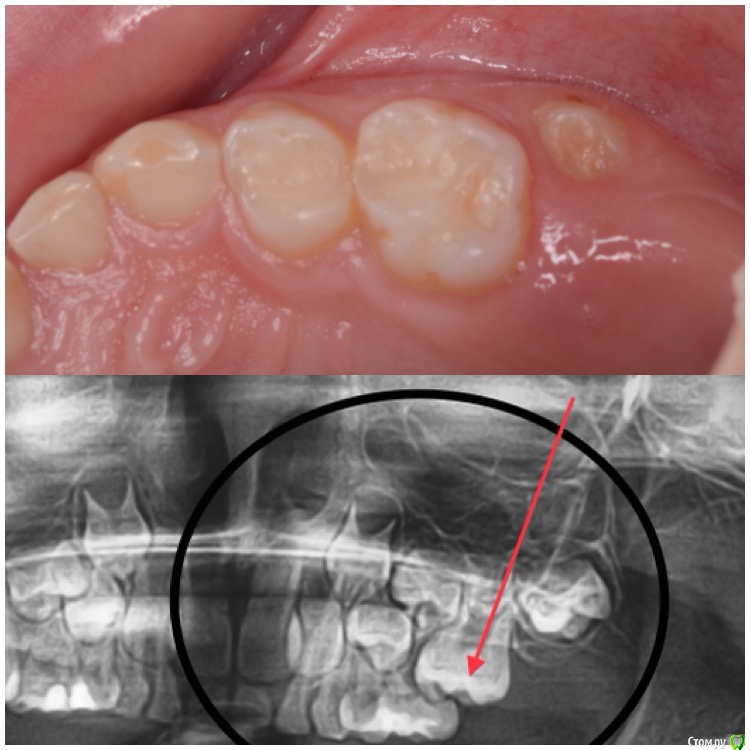

CRAZYDUCK Опубликовано 5 июня, 2018 Автор Поделиться Опубликовано 5 июня, 2018 Про эктопию верхних 6 зубов ( импактные шестые зубы). Встречается не так уж и редко . Для общего развития всем будет полезно . Эктопия ( импактные верхние 6 зубы).просто говоря - верхние 6 зубы из-за дефицита места на верхней челюсти или из-за оси прорезывания направленной медиально , способствуют резорбции корня 6.5 или 5.5. Эктопия может быть обратимой и необратимой . Но после 8 лет ( но возраст зубной может отличаться от антропометрического, поэтому смотрим на сроки прорезывания других постоянных зубов у конкретного ребёнка ) ортодонтическая коррекция нужна ( процесс необратимый). Методы устранения -Без удаления временного 5 возможно применение частичной брекет-системы , которая нормализует ось прорезывания 6 зуба ( в литературе можете найти всякие латунные сепараторы , но это история и мне кажется сложнее брекет-системы ). На первых двух фото показан случай эктопии 1.6 , который не требует удаления 5.5 . А вот дальше показан случай эктопии 2.6 , требующий удаления 6.5. Каждый случай индивидуален . ‼️коллеги , важно помнить , что 2.6 в случае удаления 6.5 полностью заблокирует зачаток 2.5 ‼️здесь обязательно нужна будет помощь ортодонта ( немедленная или отсроченная ортодонт с родителями решат ). Ну а 5 временные зубы после такой подлости со стороны шестёрок могут быть причиной воспаления ( хотя сами пятые могут быть инактными ). 2 Ссылка на комментарий

CRAZYDUCK Опубликовано 5 июня, 2018 Автор Поделиться Опубликовано 5 июня, 2018 (изменено) Про эктопию верхних 6 зубов . Изменено 5 июня, 2018 пользователем CRAZYDUCK Ссылка на комментарий